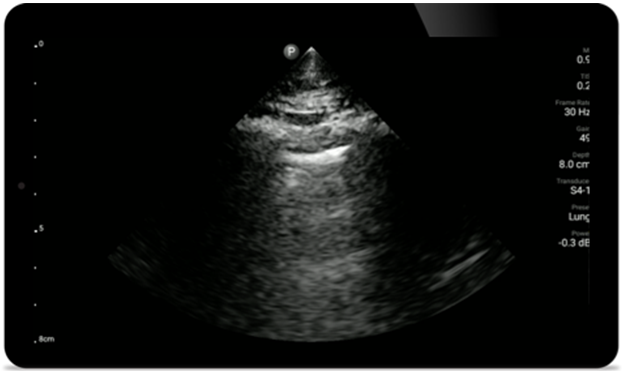

Use Lumify for airway and pulmonary assessment

Lumify POCUS solutions can help you detect the endotracheal tube within the trachea, assist in emergent cricothyrotomy procedures, diagnose pleural effusion and interstitial alveolar diseases.

Pulmonary assessment

Lumify S4-1 broadband phased array transducer

• 4 to 1 MHz extended operating frequency range

• 2D, color Doppler, M-mode, advanced XRES and multivariate harmonic imaging

• High-resolution imaging for abdominal and cardiac applications: Cardiac, OB/GYN, Lung, Abdomen and FAST imaging preset optimizations